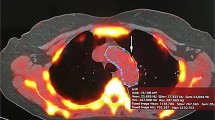

However, the patterns of calcium distribution observed in CT scans may suggest the predominance of intimal or medial calcium. Intimal calcium usually has a patchy distribution within atherosclerotic lesions and is most commonly amorphous without distinct architecture [23•]. On the other hand, vascular medial calcium is generally concentric, appears more circumferential, and has a diffuse distribution [23•]. Figure 2 shows schematically the patterns of calcium distribution in the tunica intima and media.